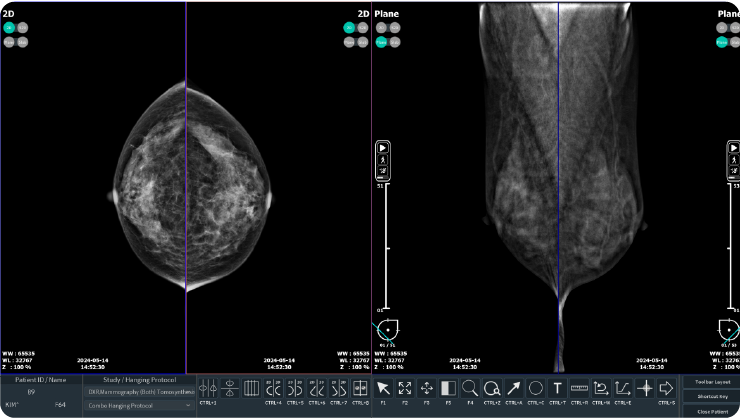

- Convenient review workstation enables quick diagnosis

- Seamless transition between imaging modes

(2D, Synthetic 2D, Slab, Plane)